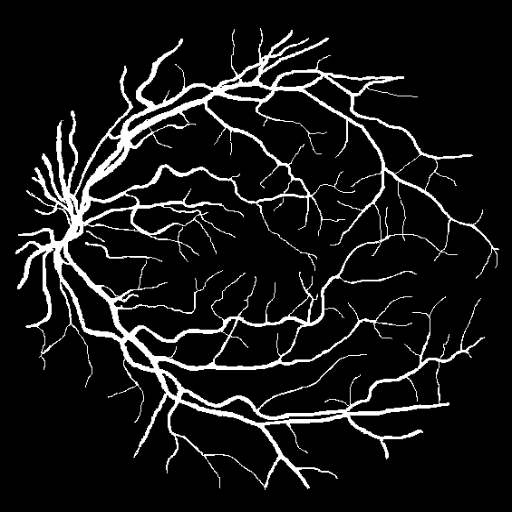

Wyniki i efekty

- Dokładność (accuracy): 89% – całkiem nieźle jak na prosty model bez głębokiego uczenia!

- Czułość (recall): 85% – dobrze wykrywał naczynia krwionośne, ale czasami mylił je z cienkimi liniami tła.

- Precyzja (precision): 91% – model dość skutecznie unikał fałszywych alarmów (błędnego oznaczania tła jako naczyń).

Wiem, że efekt na pierwszy rzut oka nie powala i można się zastanawiać, jakim cudem udało się uzyskać tak dobre “cyferki” (czyli dokładność). Ale tu właśnie tkwi mały szkopuł, czyli narzucone wymaganie.

Chciałbym zaznaczyć, że do uczenia modelu wykorzystałem wycinki o rozmiarze 3x3 pikseli, ponieważ na tak małych fragmentach model łatwiej wykrywa lokalne wzorce charakterystyczne dla naczyń krwionośnych.

Całkowity rozmiar obrazu to 512x512 pikseli, więc jeśli klasyfikator stwierdził, że dany wycinek to naczynie krwionośne, to te 9 pikseli (3x3) w rezultacie zostało w całości wypełnione na biało.